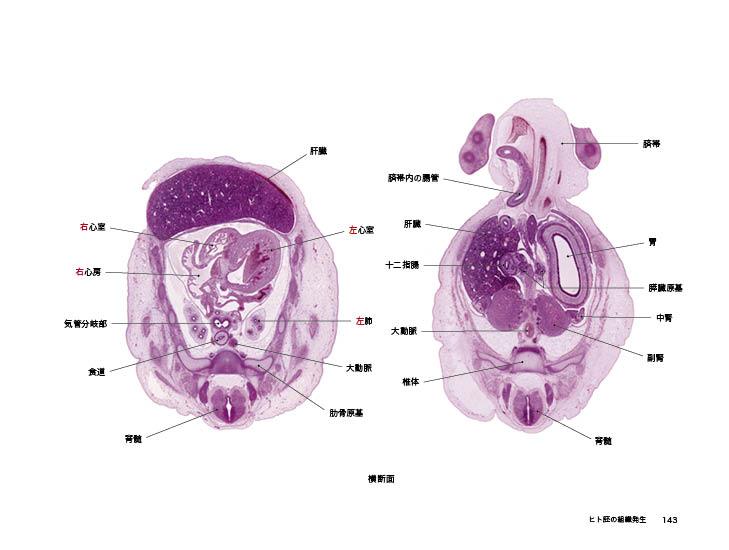

ヒト発生の3次元アトラス (3D Anatomy Project) | 塩田浩平 |本,

ヒト発生の3次元アトラス (3D Anatomy Project) | 塩田浩平 |本, ヒト発生の3次元アトラス|書籍・jmedmook|日本医事新報社,

ヒト発生の3次元アトラス|書籍・jmedmook|日本医事新報社, 解剖学 - 3Dアトラス - Anatomy 3D Atlas - Windows に無料で,